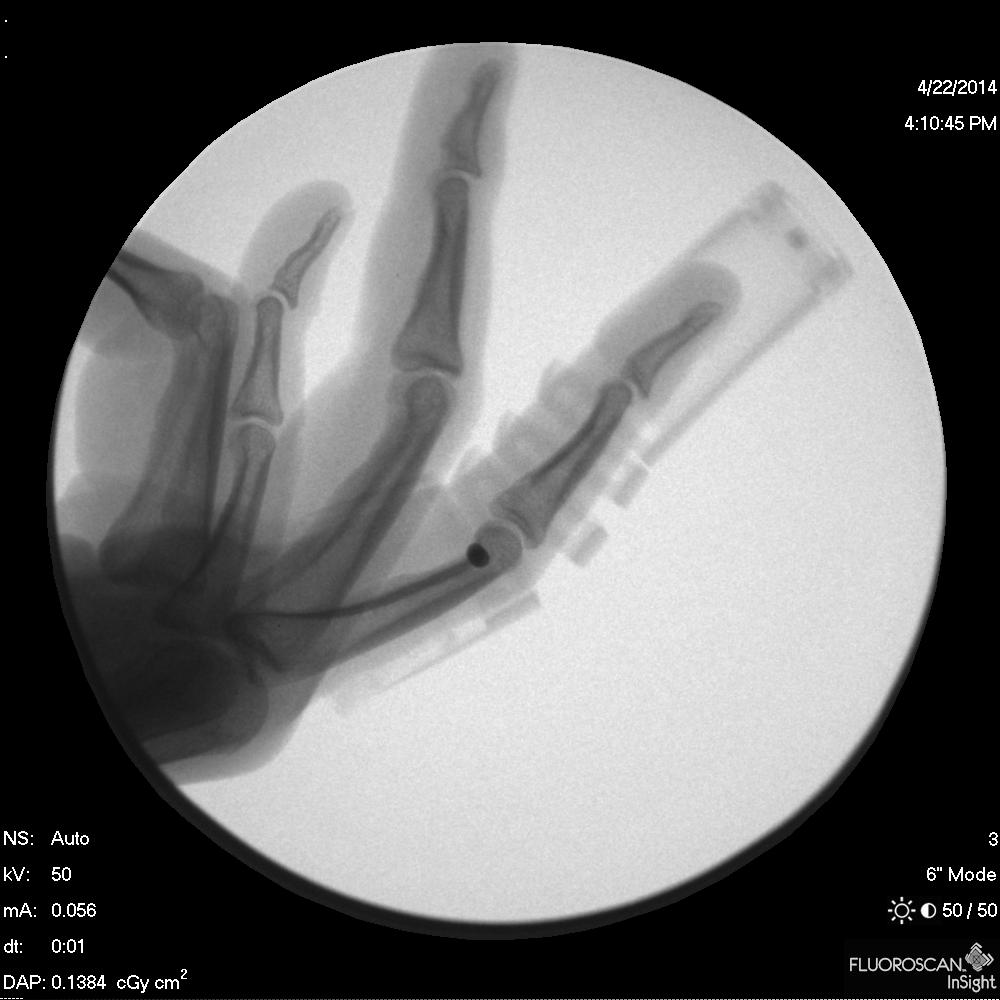

bend, a revolutionary medical finger split